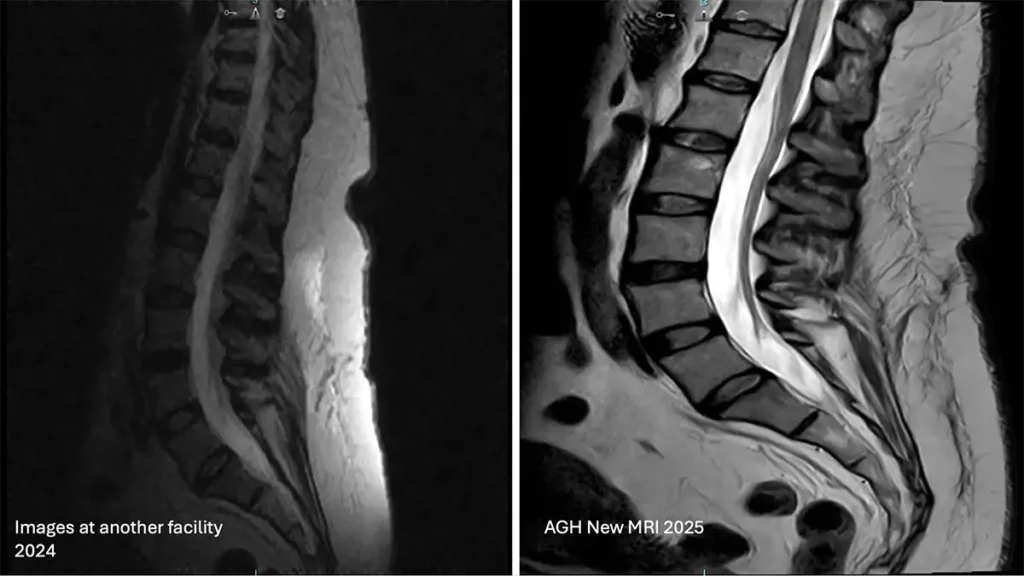

Now Featuring a State-of-the-Art MRI in Artesia NM

Artesia General Hospital now offers the Fuji Echelon 1.5T MRI system at our Artesia imaging center—currently one of only two in a hospital setting nationwide. This advanced MRI provides high-quality images with improved patient comfort. Its wide bore and table design help patients who may feel anxious or claustrophobic. The system uses deep learning for faster, clearer scans and includes non-contrast options and reduced interference from metal implants. This new MRI gives patients in Southeastern New Mexico access to cost-effective, hospital-grade technology—without the long drive.